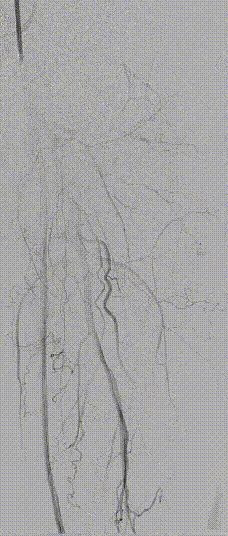

图为:2023年11月 2年后复查

2年后(2023-11)复查

下肢动脉CTA提示左股腘动脉通畅,DES区域未见内膜增生管腔丢失表现